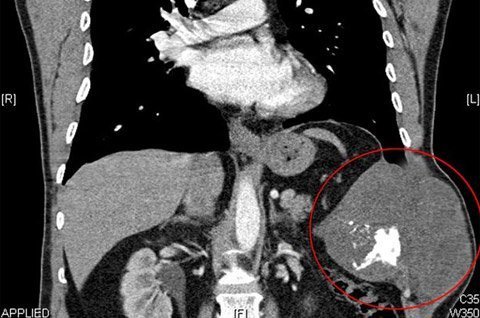

Ảnh chụp cho thấy khối u ung thư sụn ác tính (khoanh tṛn) trong lồng ngực của Marek Barden. Ảnh: Carters

Cách đây khoảng 1 năm, anh Barden nhận thấy bên sườn của ḿnh có một chỗ u lên nhưng lại phớt lờ nó v́ nghĩ đó là hậu quả của tai nạn xe đạp. Tuy nhiên, kết quả chụp cắt lớp hồi tháng 8 năm ngoái hé lộ, anh có một khối u ung thư sụn ác tính (chondrasarcoma).